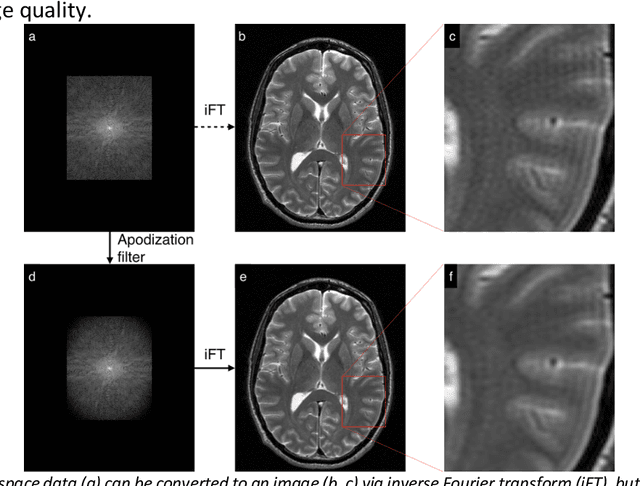

Abstract:A novel deep learning-based magnetic resonance imaging reconstruction pipeline was designed to address fundamental image quality limitations of conventional reconstruction to provide high-resolution, low-noise MR images. This pipeline's unique aims were to convert truncation artifact into improved image sharpness while jointly denoising images to improve image quality. This new approach, now commercially available at AIR Recon DL (GE Healthcare, Waukesha, WI), includes a deep convolutional neural network (CNN) to aid in the reconstruction of raw data, ultimately producing clean, sharp images. Here we describe key features of this pipeline and its CNN, characterize its performance in digital reference objects, phantoms, and in-vivo, and present sample images and protocol optimization strategies that leverage image quality improvement for reduced scan time. This new deep learning-based reconstruction pipeline represents a powerful new tool to increase the diagnostic and operational performance of an MRI scanner.